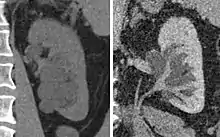

| Renal cyst of the left kidney (hyperintense area) as shown on MRI. | |